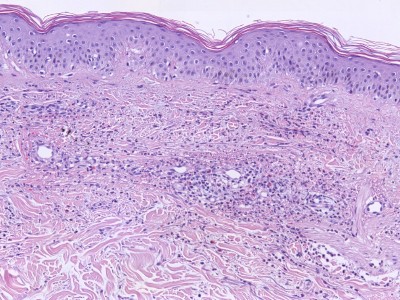

Leukocytoclastische vasculitis (vasculitis allergica) is een verzamelnaam voor een heterogene groep systemische, cutane of gemengd cutane/systemische aandoeningen die als gemeenschappelijk histopathologisch criterium een ontsteking van arteriolen, capillairen, en venulen hebben. Cutaneous Small Vessel Vasculitis (CSVV) is een klinisch begrip, bedoeld wordt een vasculitis (niet nader omschreven, meestal leukocytoclastisch) van de kleine vaten, beperkt tot de huid. De belangrijkste PA-kenmerken van leukocytoclastische vasculitis zijn: leukocytair perivasculair infiltraat (soms lymfocytair, soms eosinofiel), gezwollen endotheelcellen, fibrinoide necrose van de vaatwand, kernpuin rond de vaten (leukocytoclasie), erytrocyten extravasatie, en getromboseerde vaten. Zie ook onder vasculitis.

Histologie leukocytoclastische vasculitis Histologie leukocytoclastische vasculitis Histologie leukocytoclastische vasculitis

ingescande coupe (zoom) ingescande coupe (zoom) ingescande coupe (zoom)